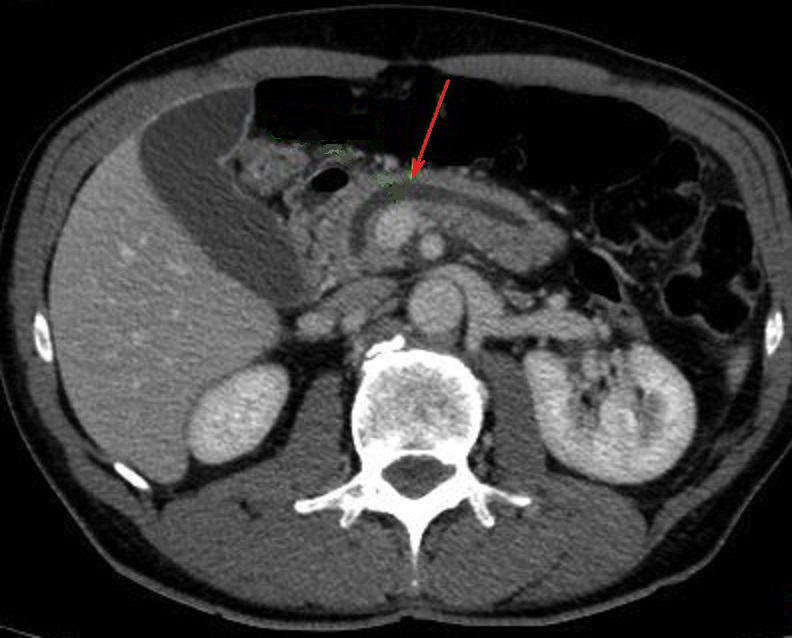

Image

radiologique TDM d'une TIPMP type canaux

secopndaire du cord pancreas a aspect lesionnel de

kyste liquidienne ovalaire hypoidensite a bord

regulier , fine en vue tres nette du corp du

pancreas ( fleche rouge ), sa paroi ne se

rehaussement apres injection de contras

intraveineuse . Image radiologique TDM plus C+

en coupe axiale . |